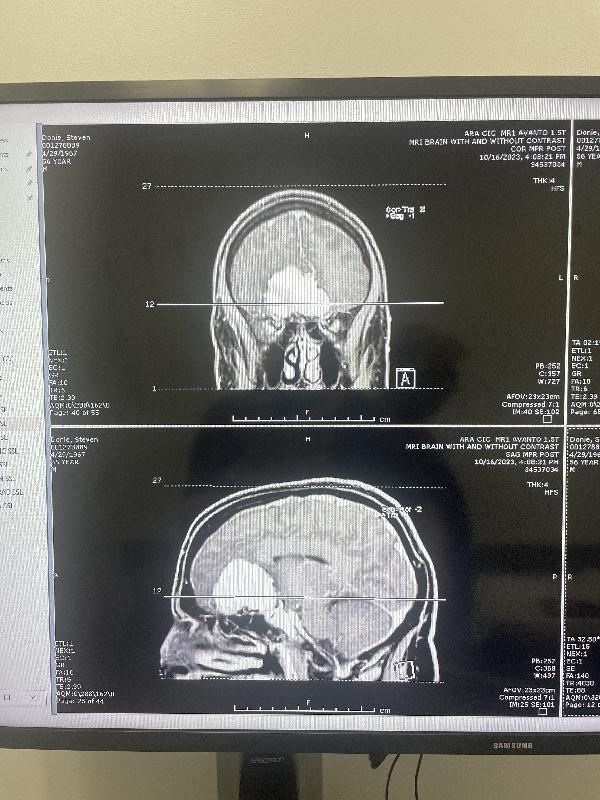

MRI, front and side views

This shows the tumor just above my nose. One of the side effects was that I lost my sense of smell. I had noticed that before the memory symptoms, but I first noticed it during the COVID outbreak, and attributed it to that. The surgeon said it is unlikely I will get my smell back.